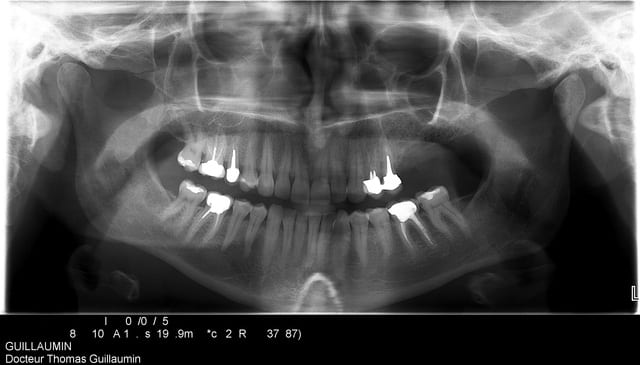

voici juste pour commencer la présentation du cas..

50 ans, fumeuse, belle femme, CBS suite à une malheureuse extraction

fermeture de la cbs par un chir maxillo-faciale à l'aide de la boule de Bichat

6 ans plus tard elle se plaint de gênes à ce niveau.

elle veut des dents.

Karine panoramic1 qukyq7 - Eugenol

Karine axial hugayu - Eugenol

Karine overview bwnmay - Eugenol

Karine 3d lehmdt - Eugenol

Karine cross section pvx9dd - Eugenol